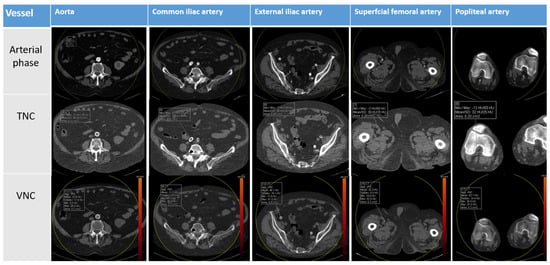

| Anatomical Region | Contrast Phase | Mean Attenuation (HU) | Standard Deviation (DS) | p |

|---|---|---|---|---|

| Aorta | TNC | 47.1 | 6.6 | <0.000 |

| VNC | 33.0 | 8.2 | ||

| AIC | TNC | 47.8 | 8.9 | <0.000 |

| VNC | 34.1 | 11.4 | ||

| AIE | TNC | 46.6 | 9.4 | <0.27 |

| VNC | 33.1 | 6.4 | ||

| AFS | TNC | 48.5 | 9.0 | <0.001 |

| VNC | 38.2 | 10.4 | ||

| AP | TNC | 49.4 | 7.8 | <0.000 |

| VNC | 40.7 | 9.6 |